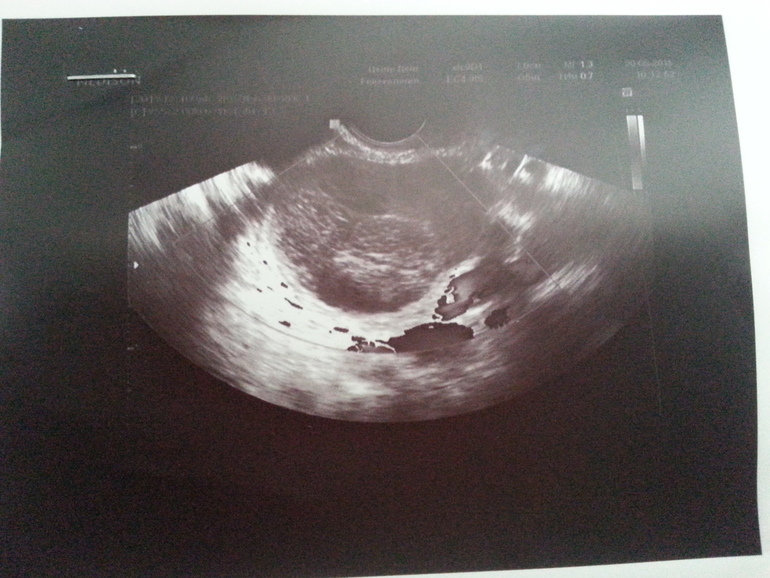

а картинка есть?\\покажите?может и фолликул перерасти был.

c2431d1d8458db9c5fa586451ee000bd.jpg

точно киста жт, да бывают задержки и температуру держит киста, она очень много прогестерона выделяет.наберитесь терпения.